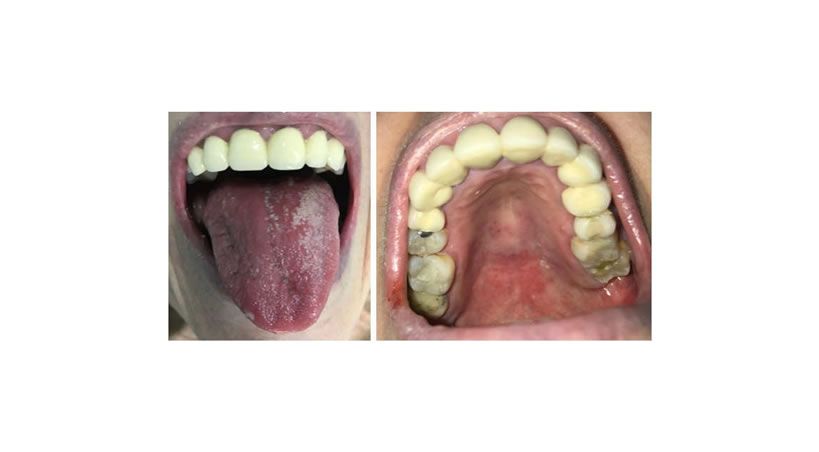

Cuidado bucal para proteger a las personas con enfermedades crónicas

La evidencia científica afirma que las alteraciones en la salud oral repercuten en morbilidades como la diabetes, hipertensión, entre otras.